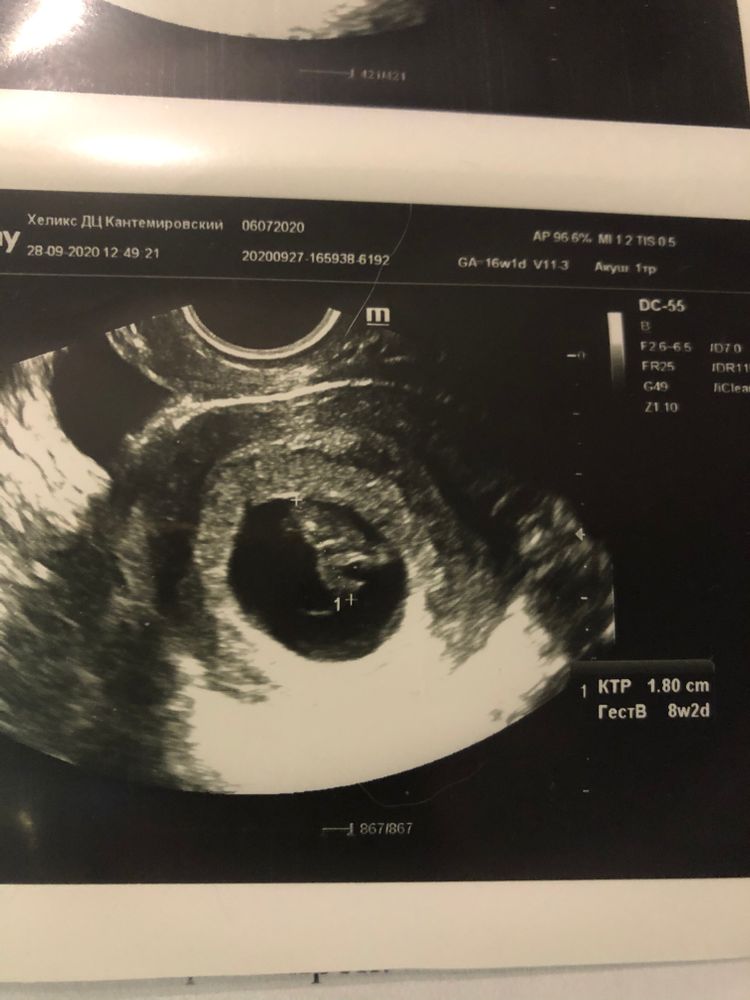

8 недель и 2 дня, опять УЗИ

Юлия, это третий раз был. Первое УЗИ делала в 5 недель чтобы подтвердить Б, потом в 7 проверить СБ и вот сейчас из-за переживашек пошла. Ну если бы пошла к своему врачу с этим всем он бы все равно сам узи сделал.